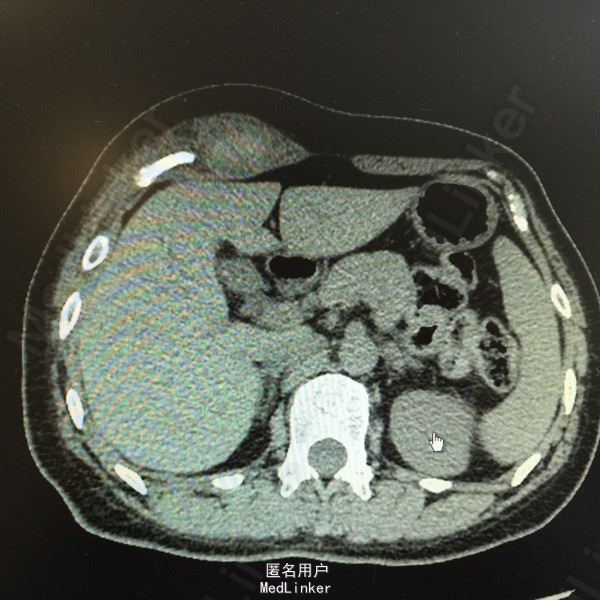

主诉:腹痛、发现腹部肿物15天。 现病史:患者于15天前因运动后突发腹痛,为持续性胀痛,伴停止排气,无恶心、呕吐,后觉疼痛缓解,并发现腹部肿物,压痛明显。当时于外院行超声:右上腹患者所指处肌层见无回声,约8*6cm大小,形态规则,边界清。现患者无诉疼痛,自觉肿块变小,为进一步诊治,收入我科。 既往史、家族史均无特殊。 查体:全腹软,右上腹近季肋部可触及一5*2cm包块,质软,活动差,压痛明显,周围皮肤无红肿、无溃烂。余无特殊。 辅助检查: 超声:患者右上腹腹壁层内肌层后方见无回声,大小约5.4*2.3cm,形态规则,边界尚清,内见少许分隔。考虑右上腹腹壁内囊性包块。 CT:右上腹季肋部腹直肌鞘内梭形软组织密度影,病变中央密度高,约65HU,边缘密度稍低,约33HU。印象:右上腹腹直肌鞘内梭形高密度影,血肿不除外。 大家考虑?